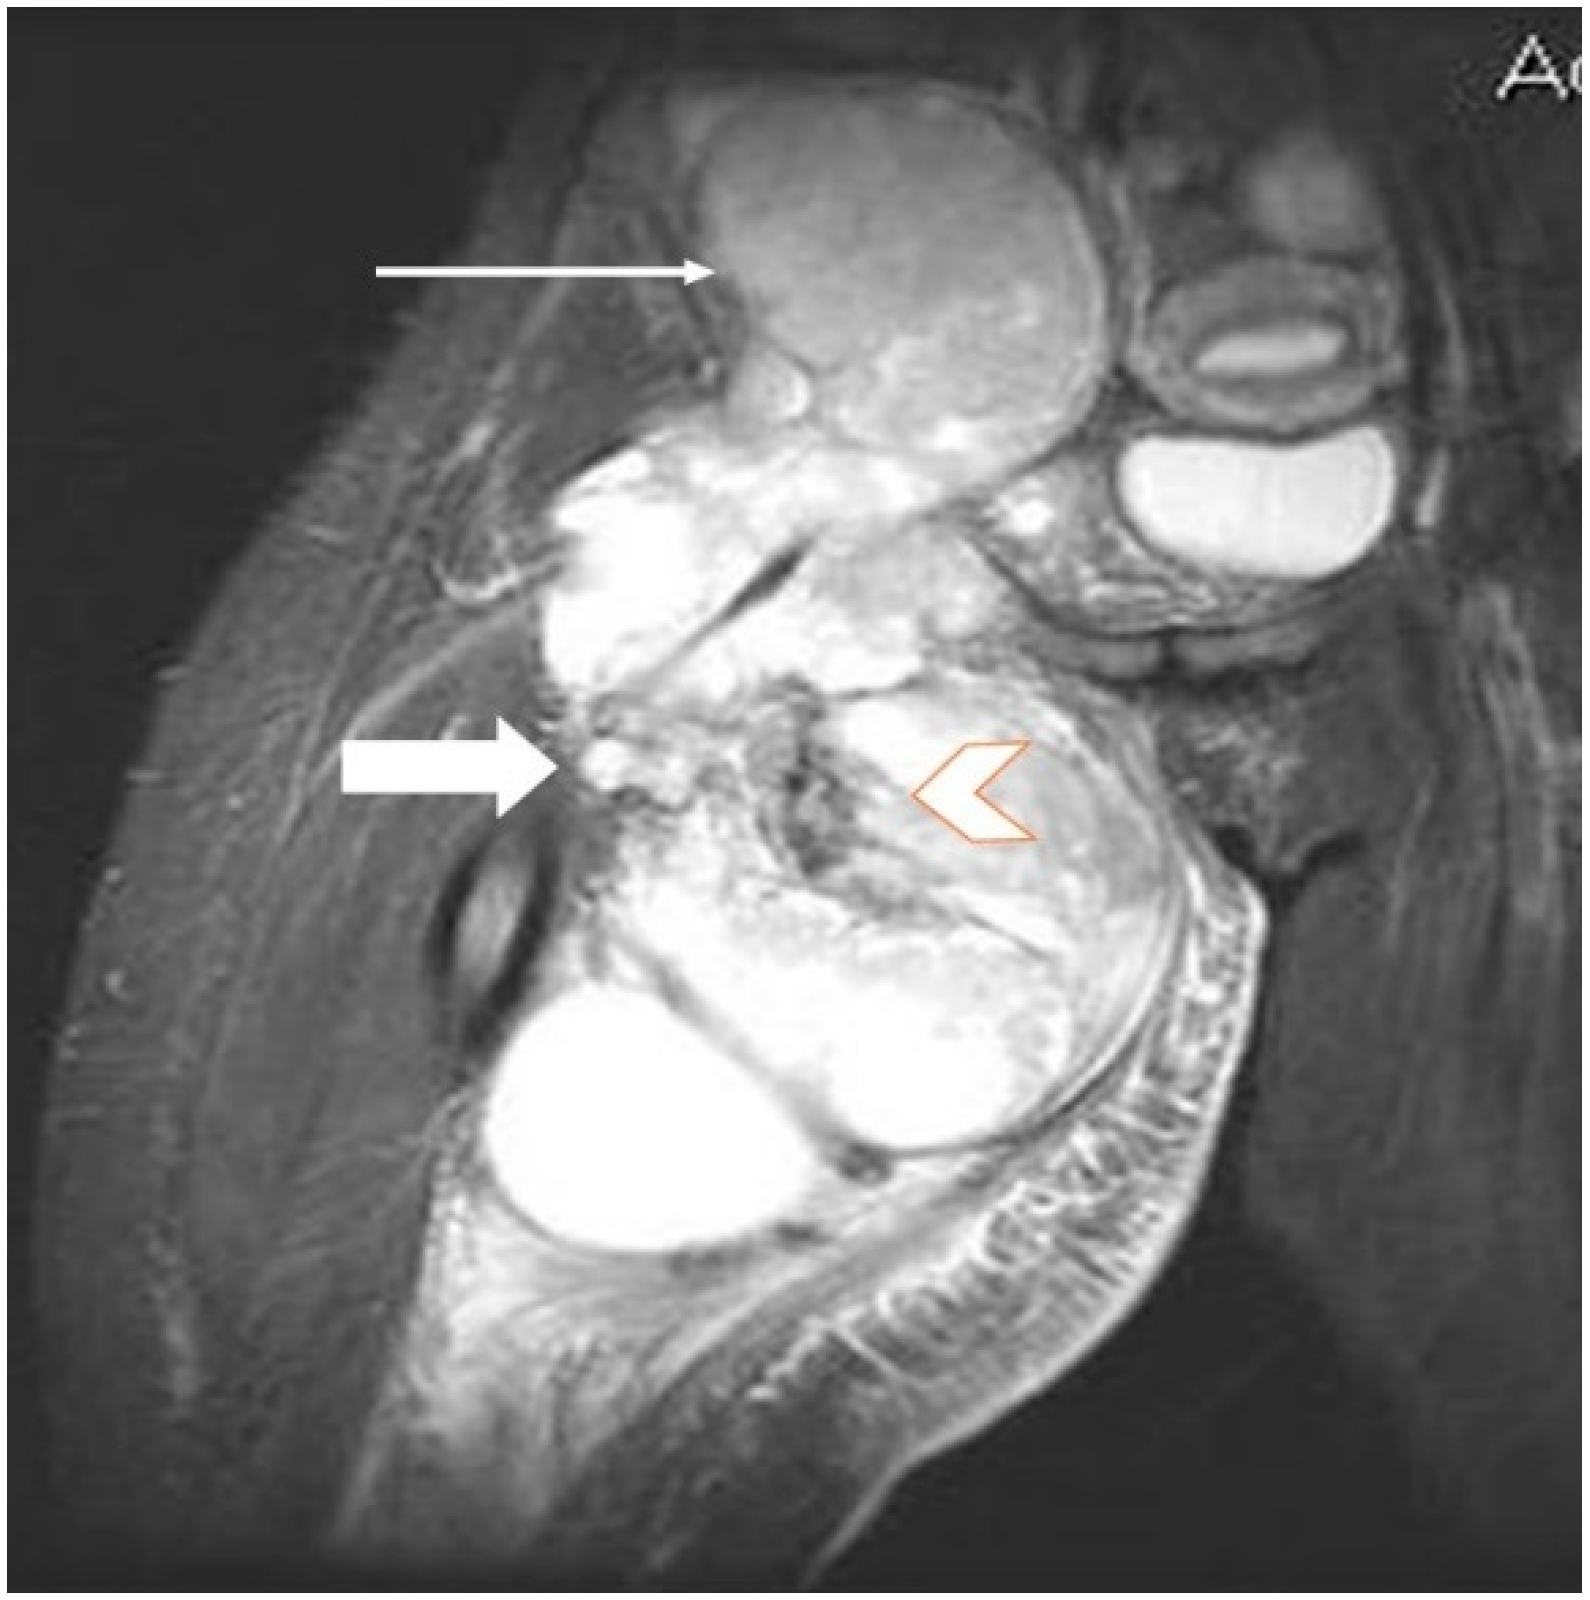

2.2. Imaging Examinations